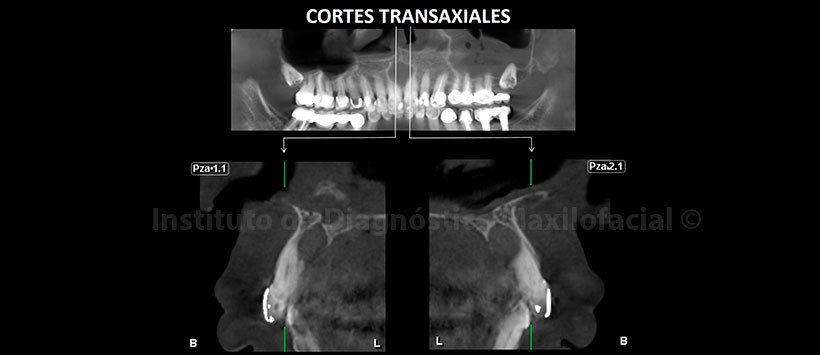

A la evaluación de la tomografía volumétrica (CBCT) en cortes multiplanares (Figura 2) y transaxiales (Figura 3), se evidencia un aumento de tamaño del conducto nasopalatino en sentido mesio-distal y cefálico caudal con un volumen aproximado de 0.5cm3 (Figura 4), ocasiona una ligera expansión, adelgazamiento y zonas de erosión de la tabla ósea palatina; también se visualiza una relación estrecha con los ápices de las piezas 1.1 y 2.1.